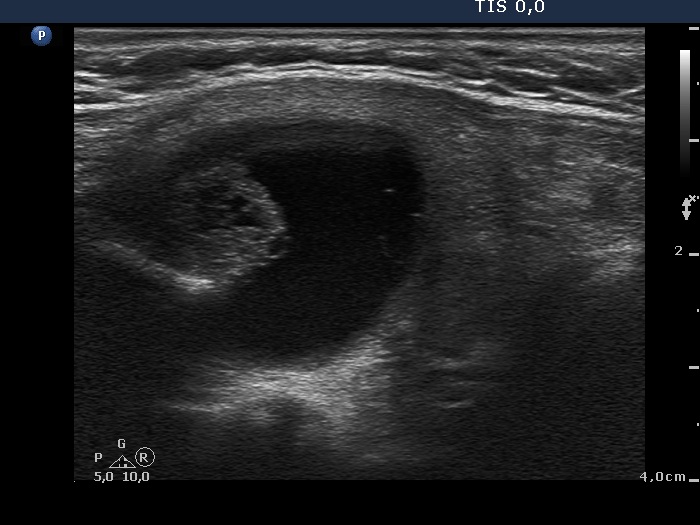

Benign Hashimoto's thyroiditis (cytological diagnosis) - case 1652

First, we demonstrate two cases of Hashimoto's thyroiditis with pronounced fibrotic changes. Both present pale and bright hyperechogenic granules and lines corresponding to normal and excessive connective tissue. Neither of the discrete areas are nodules in a pathological sense.